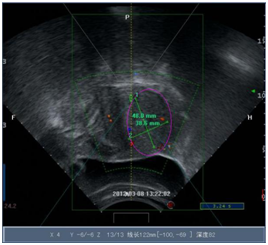

门诊定位确定甘女士能做海扶后,甘女士于2012年3月在湖北省妇幼保健院接受了海扶治疗。